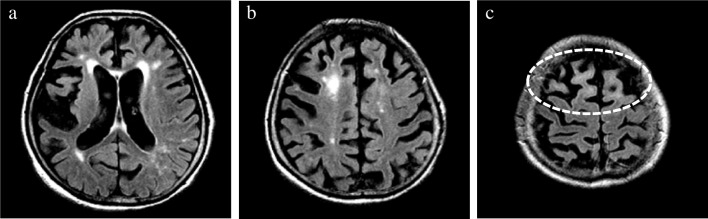

In addition, the presence/absence of subcortical white matter hyperintensity (SWMH) was visually evaluated on axial FLAIR images [ref. 24, ref. 25]. Considering that hyperintensity in the periventricular and deep white matter can be attributed to aging and cerebral small vessel disease (i.e., leukoaraiosis), signal changes confined to the subcortical white matter were exclusively evaluated (Fig. 3).